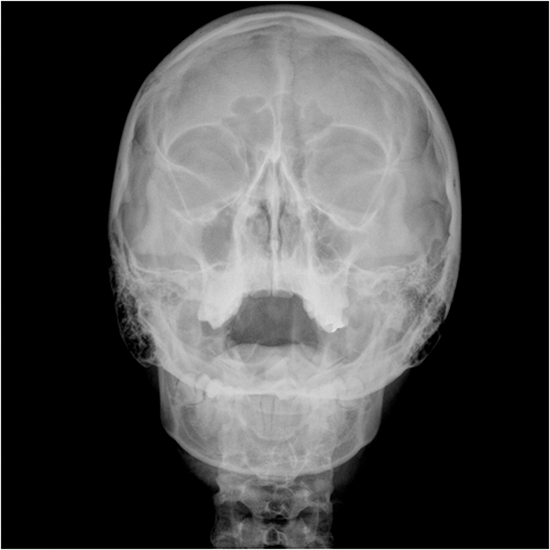

An X-ray of the optic foramen is a safe and painless way to look at the opening of the optic canal at the base of the skull. This opening is called the optic foramen. The optic nerve and the ophthalmic artery go through the optic canal and into the orbital cavity.

This test is given to see if any of the bones around the optic foramen have broken and to check for any changes in the shape or size of the optic canal that could put pressure on the nerves and arteries that pass through it. This test can help determine if you have optic neuropathy or might have an infection.